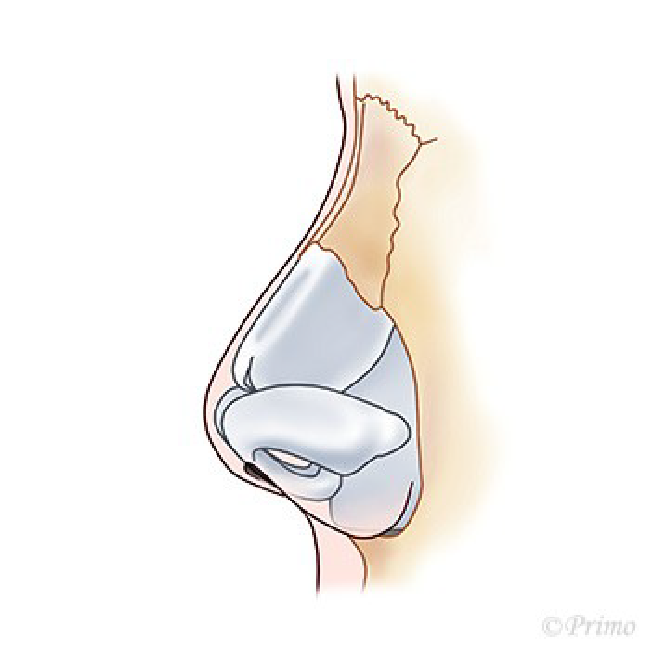

鼻中隔延長術を行った後、感染や何らかの原因で強い炎症を伴って鼻先が拘縮してしまった場合、時期を待って肋軟骨移植による修正を行う方法があります。

拘縮し鼻先や鼻尖が後退している状態の改善を図るため、open approachから拘縮をできるだけ解除します。

肋軟骨で作成したL型フレームを移植します。

肋軟骨L型フレームを外側鼻軟骨と前鼻棘に縫合固定します。

鼻翼軟骨をL型フレームに引き上げ固定します。

必要に応じて鼻柱部分に軟骨移植を追加します。

鼻先を耳介軟骨や軟部組織でカバーします。